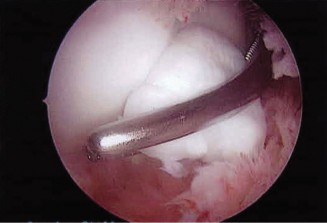

CT arthrograms of the patient’s left shoulder are shown in Figure 2–56. CRP is <3, ESR 45. The patient continues to have pain, so you decide to perform arthroscopic biopsy to obtain tissue cultures. Frozen sections show <5 PMNs per hpf, and Gram stains are all negative.

Figure 2–56

The correct answer is (B). Figure shows contrast under the glenoid component. Given the patient’s normal inflammatory markers and frozen sections combined with continued pain and loosening on CT, infection with P. acnes(an organism that is very difficult to isolate) should be investigated by holding any cultures for at least 2 weeks to see if it will eventually grow. Chocolate agar (Choice C) is mainly used for growing species such as H. influenzae and Neisseria meningitidis not P. acnes. A is incorrect since the patient’s cell count and frozen sections are clearly abnormal, therefore referral to pain clinic would not be appropriate. However, Choice D would be too aggressive an approach given that no organisms have been isolated, frozen sections show <5 PMNs per hpf, and the patient has relatively normal inflammatory markers.